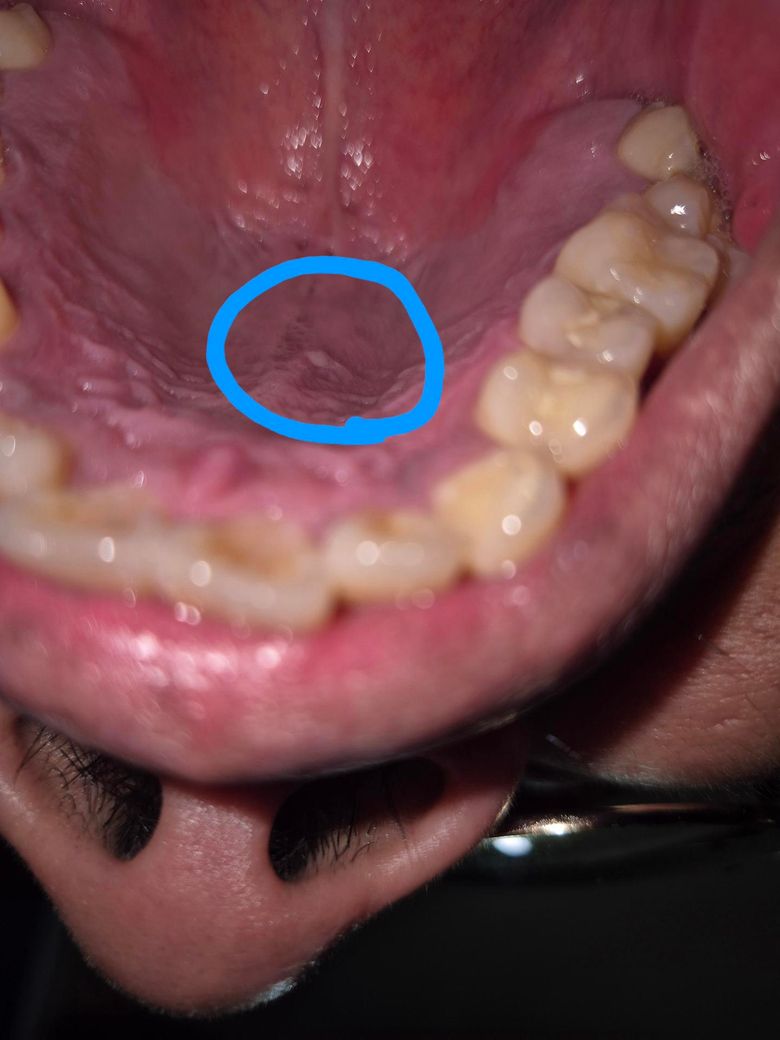

하얀물집같은게 생겼어요 뭘까요??

통증은 없어요 최근에 생긴듯해요

피곤해서 생긴걸까요? 뜨거운음식 최근에 자주먹긴했는데용...............

올려주신 사진에서 병변이 잘 확인되진 않으나 구내염의 가능성이 생각됩니다.

과도한 스트레스, 과로, 음주, 흡연, 자극적인 음식의 섭취 등이 원인이 될 수 있습니다.

충분한 휴식을 취하고 균형 잡힌 영양을 섭취하며 증상 회복을 지연 시키고 통증을 악화 시킬 수 있는 음식 섭취나 생활습관은 피할 것을 권합니다.